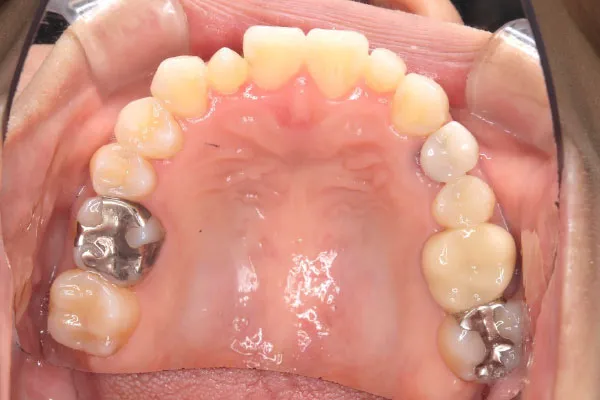

【40代女性】

反対咬合と内側の歯を

インビザライン矯正で

治療したケース

治療後

| 主訴 | 反対咬合 内側に歯がある |

|---|---|

| 期間 | 2年 |

| 費用 | 220,000円〜660,000円 (デンタルローン 3,100〜6,600円/月) |

| 治療内容 | インザライン矯正 非抜歯 |

| 治療に伴うリスク | 矯正終了後は、リテーナーを指示通りに使用し、歯の後戻りを防ぐ必要があります。 |